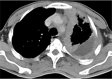

A pleural effusion is an excessive accumulation of fluid in the pleural space. It can pose a diagnostic dilemma to the treating physician because it may be related to disorders of the lung or pleura, or to a systemic disorder. Patients most commonly present with dyspnea, initially on exertion, predominantly dry cough, and pleuritic chest pain. To treat pleural effusion appropriately, it is important to determine its etiology. However, the etiology of pleural effusion remains unclear in nearly 20% of cases. Thoracocentesis should be performed for new and unexplained pleural effusions. Laboratory testing helps to distinguish pleural fluid transudate from an exudate. The diagnostic evaluation of pleural effusion includes chemical and microbiological studies, as well as cytological analysis, which can provide further information about the etiology of the disease process. Immunohistochemistry provides increased diagnostic accuracy. Transudative effusions are usually managed by treating the underlying medical disorder. However, a large, refractory pleural effusion, whether a transudate or exudate, must be drained to provide symptomatic relief. Management of exudative effusion depends on the underlying etiology of the effusion. Malignant effusions are usually drained to palliate symptoms and may require pleurodesis to prevent recurrence. Pleural biopsy is recommended for evaluation and exclusion of various etiologies, such as tuberculosis or malignant disease. Percutaneous closed pleural biopsy is easiest to perform, the least expensive, with minimal complications, and should be used routinely. Empyemas need to be treated with appropriate antibiotics and intercostal drainage. Surgery may be needed in selected cases where drainage procedure fails to produce improvement or to restore lung function and for closure of bronchopleural fistula.